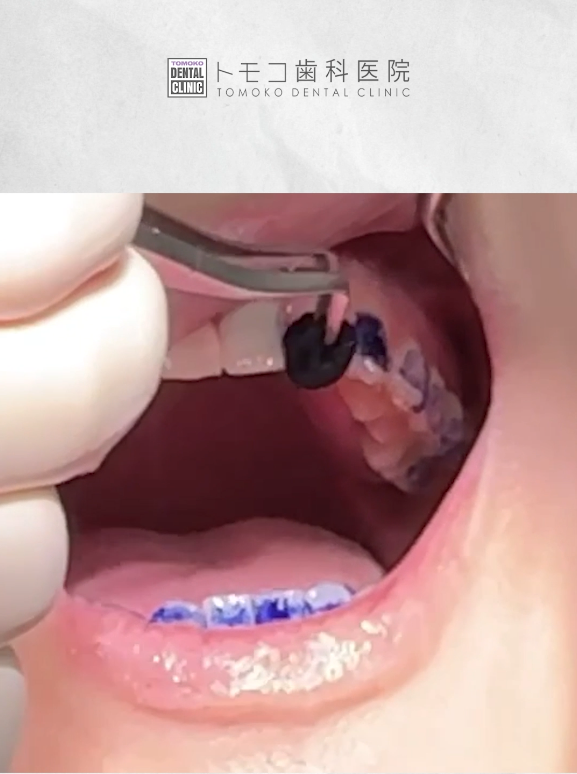

歯面染色剤を塗ったあと、

磨き残しのある部分を確認します。